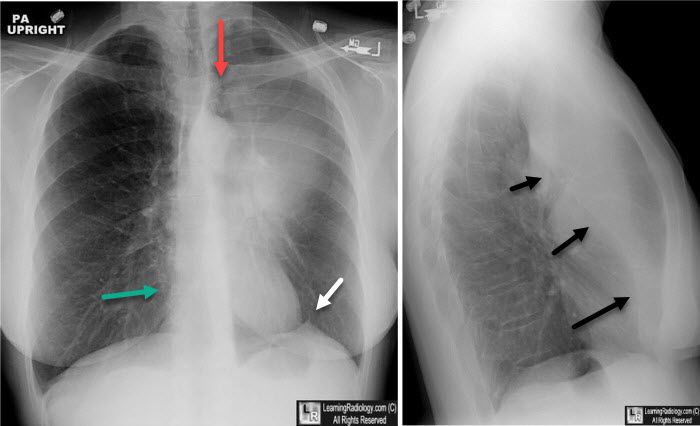

Luftsichel sign is derived from german word 'luft' which means air. It refers to a feature present on chest radiograph which arises as a result of hyperinflation of superior portion of left lower lobe. Luftsichel sign may be present in the following conditions: - left upper lobe collapse - lung malignancy - pneumomediastinum - right lung herniation Reference: https://radiopaedia.org/articles/luftsichel-sign-lungs?lang=us Image via: https://radiopaedia.org/cases/left-upper-lobe-collapse-14